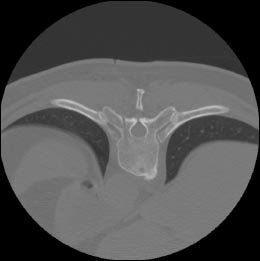

FIGURE 2OnControl needle in the CT-targeted vertebral body (

top

). Post-biopsy at same vertebral body showing the resultant bone channel after removal of bone plug specimen (

bottom

). Images courtesy of Dr. Symington.